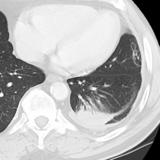

Microatelectasis (under debate)